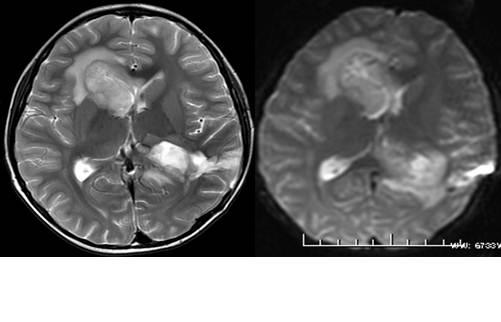

相较于“落魄”的过去,如今的放射科绝对是一众科室中的“土豪”:拥有三台DR拍片机,分别置于科室内、体检中心及体检车上,极大地拓宽了服务范围;当初的2排CT升级为德国进口的64排,且增加至2台,原本患者长达40秒的屏气如今仅需约10秒;核磁共振仪也由原来的国产低场更新为美国进口的GE新型1.5T高场,图象质量及扫描速度今非昔比,肺小结节等的诊断率大幅提升。

设备更新了,诊断范围及水平也紧跟其上。从前需省市级医院完成的穿刺活检,如今在科室人员经验积累及自我技能积极填充的基础上,已能够实现独立作业。科室目前已开展肺小结节重建、冠状动脉CTA(冠状动脉CT造影检查)、其他血管CTA(血管CT造影检查)等多个项目,且诊断水平居嘉兴市前列。正在筹备中的DSA项目将对血管介入疗法的实现起到举足轻重的推动作用,届时,水平将能提升至省级甚至国内先进。